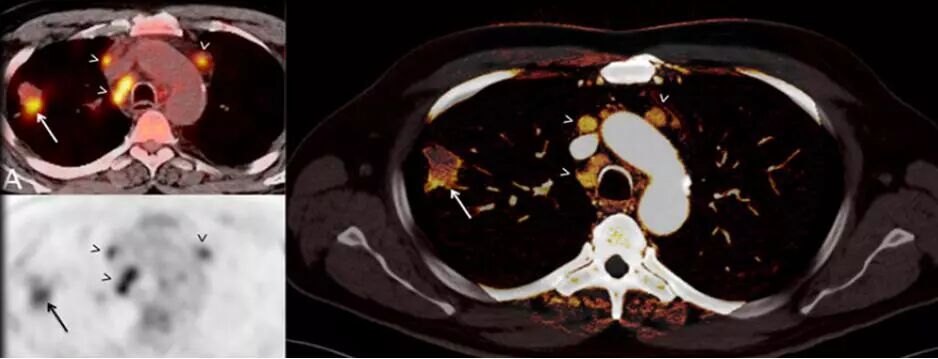

7. 類PET 成像:

傳統(tǒng)PET成像存在輻射劑量過高、放射污染、價格昂貴等局限性。

SOMATOMForce的純譜雙能量成像技術(shù)具有更好的靈敏度和特異性,使CT雙能量的應(yīng)用上升到一個前所未有的水平,應(yīng)用范圍更廣泛,不但可以常規(guī)對腫瘤組織類型、心血管疾病進行更為精確的識別,更是突破影像界限,首次實現(xiàn)碘、鈣、水、脂肪、鐵等多物質(zhì)多元素多參數(shù)量化成像,能夠精準評估骨髓挫傷水腫、腫瘤浸潤活性。

△提高診斷準確性-肺結(jié)節(jié)能量碘圖